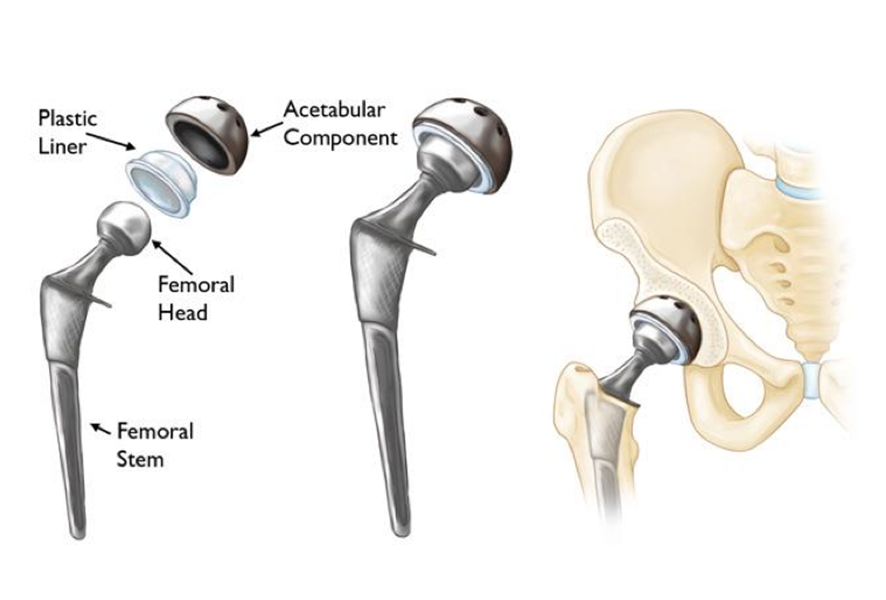

Total Hip Replacement Surgery Anatomical Acetabular Stock Vector

What Is A Joint Replacement Elite Sports Medicine Orthopedics

Total Hip Replacement BJISG

Total Hip Replacement Hip Osteoarthritis